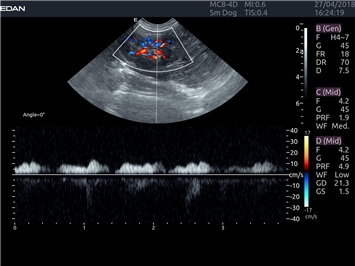

Энергетический допплер:

Да

Цветовой допплер:

Импульсно-волновой допплер:

Триплексное сканирование: